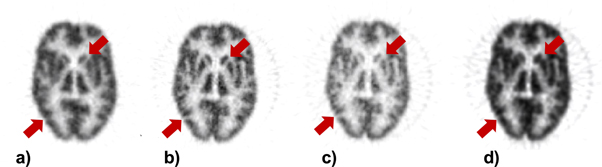

Standard image High-resolution imageThe reconstructed images of the Hoffman 3D brain phantom for the different configurations are illustrated in figure 6. The configuration with a large gantry (high-sensitivity and high-resolution detector modules) showed better image quality providing the highest anatomical details preservation relative to the Biograph mCT. As an example, the Caudate and Putamen regions are more distinguishable from each other and other regions. The scanner with a small gantry and high-resolution detector modules shows better image quality compared to the one with high-sensitivity detector modules, while it may lead to underestimation of radiotracer uptake (the red arrow in the occipital lobe).

Figure 6. Reconstructed images of the Hoffman 3D brain phantom corresponding to the geometry of: (a) the Biograph mCT, (b) configuration with large gantry including high-sensitive and high-resolution detectors (c) configuration with small-gantry and high-resolution detectors, (d) configuration with small gantry and high-sensitivity detectors. The red arrows indicate two regions presenting different uptake patterns for image obtained on each scanner.